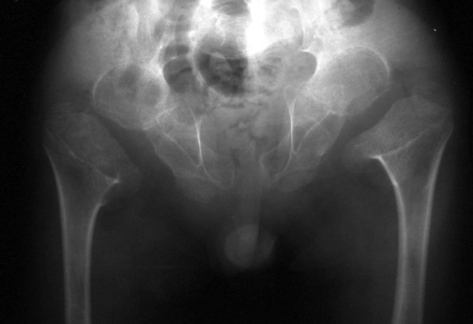

Fig.2. Ausência das epífises femorais capitais, alargamento das metáfises e da sínfise púbica e uma pélvis estreita. Créditos: Sciencedirect